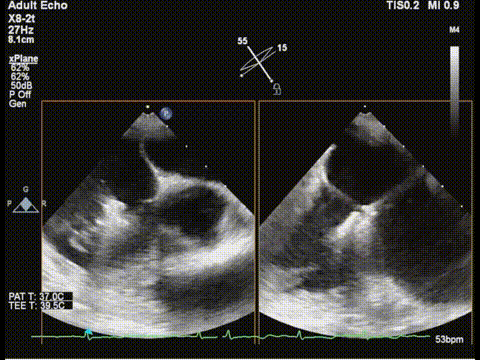

随后,团队将操作重点转向三尖瓣。在胃底食道超声界面引导下,调整夹合器位置并成功跨瓣,在确保充分捕捉前叶与膈叶后释放夹合器。术后三尖瓣反流明显减轻,遂完全释放夹合器,手术顺利成功。

调整胃底界面评估三尖瓣夹子位置

夹合器钳夹三尖瓣瓣叶后评估

释放三尖瓣架子

三尖瓣架子释放后评估